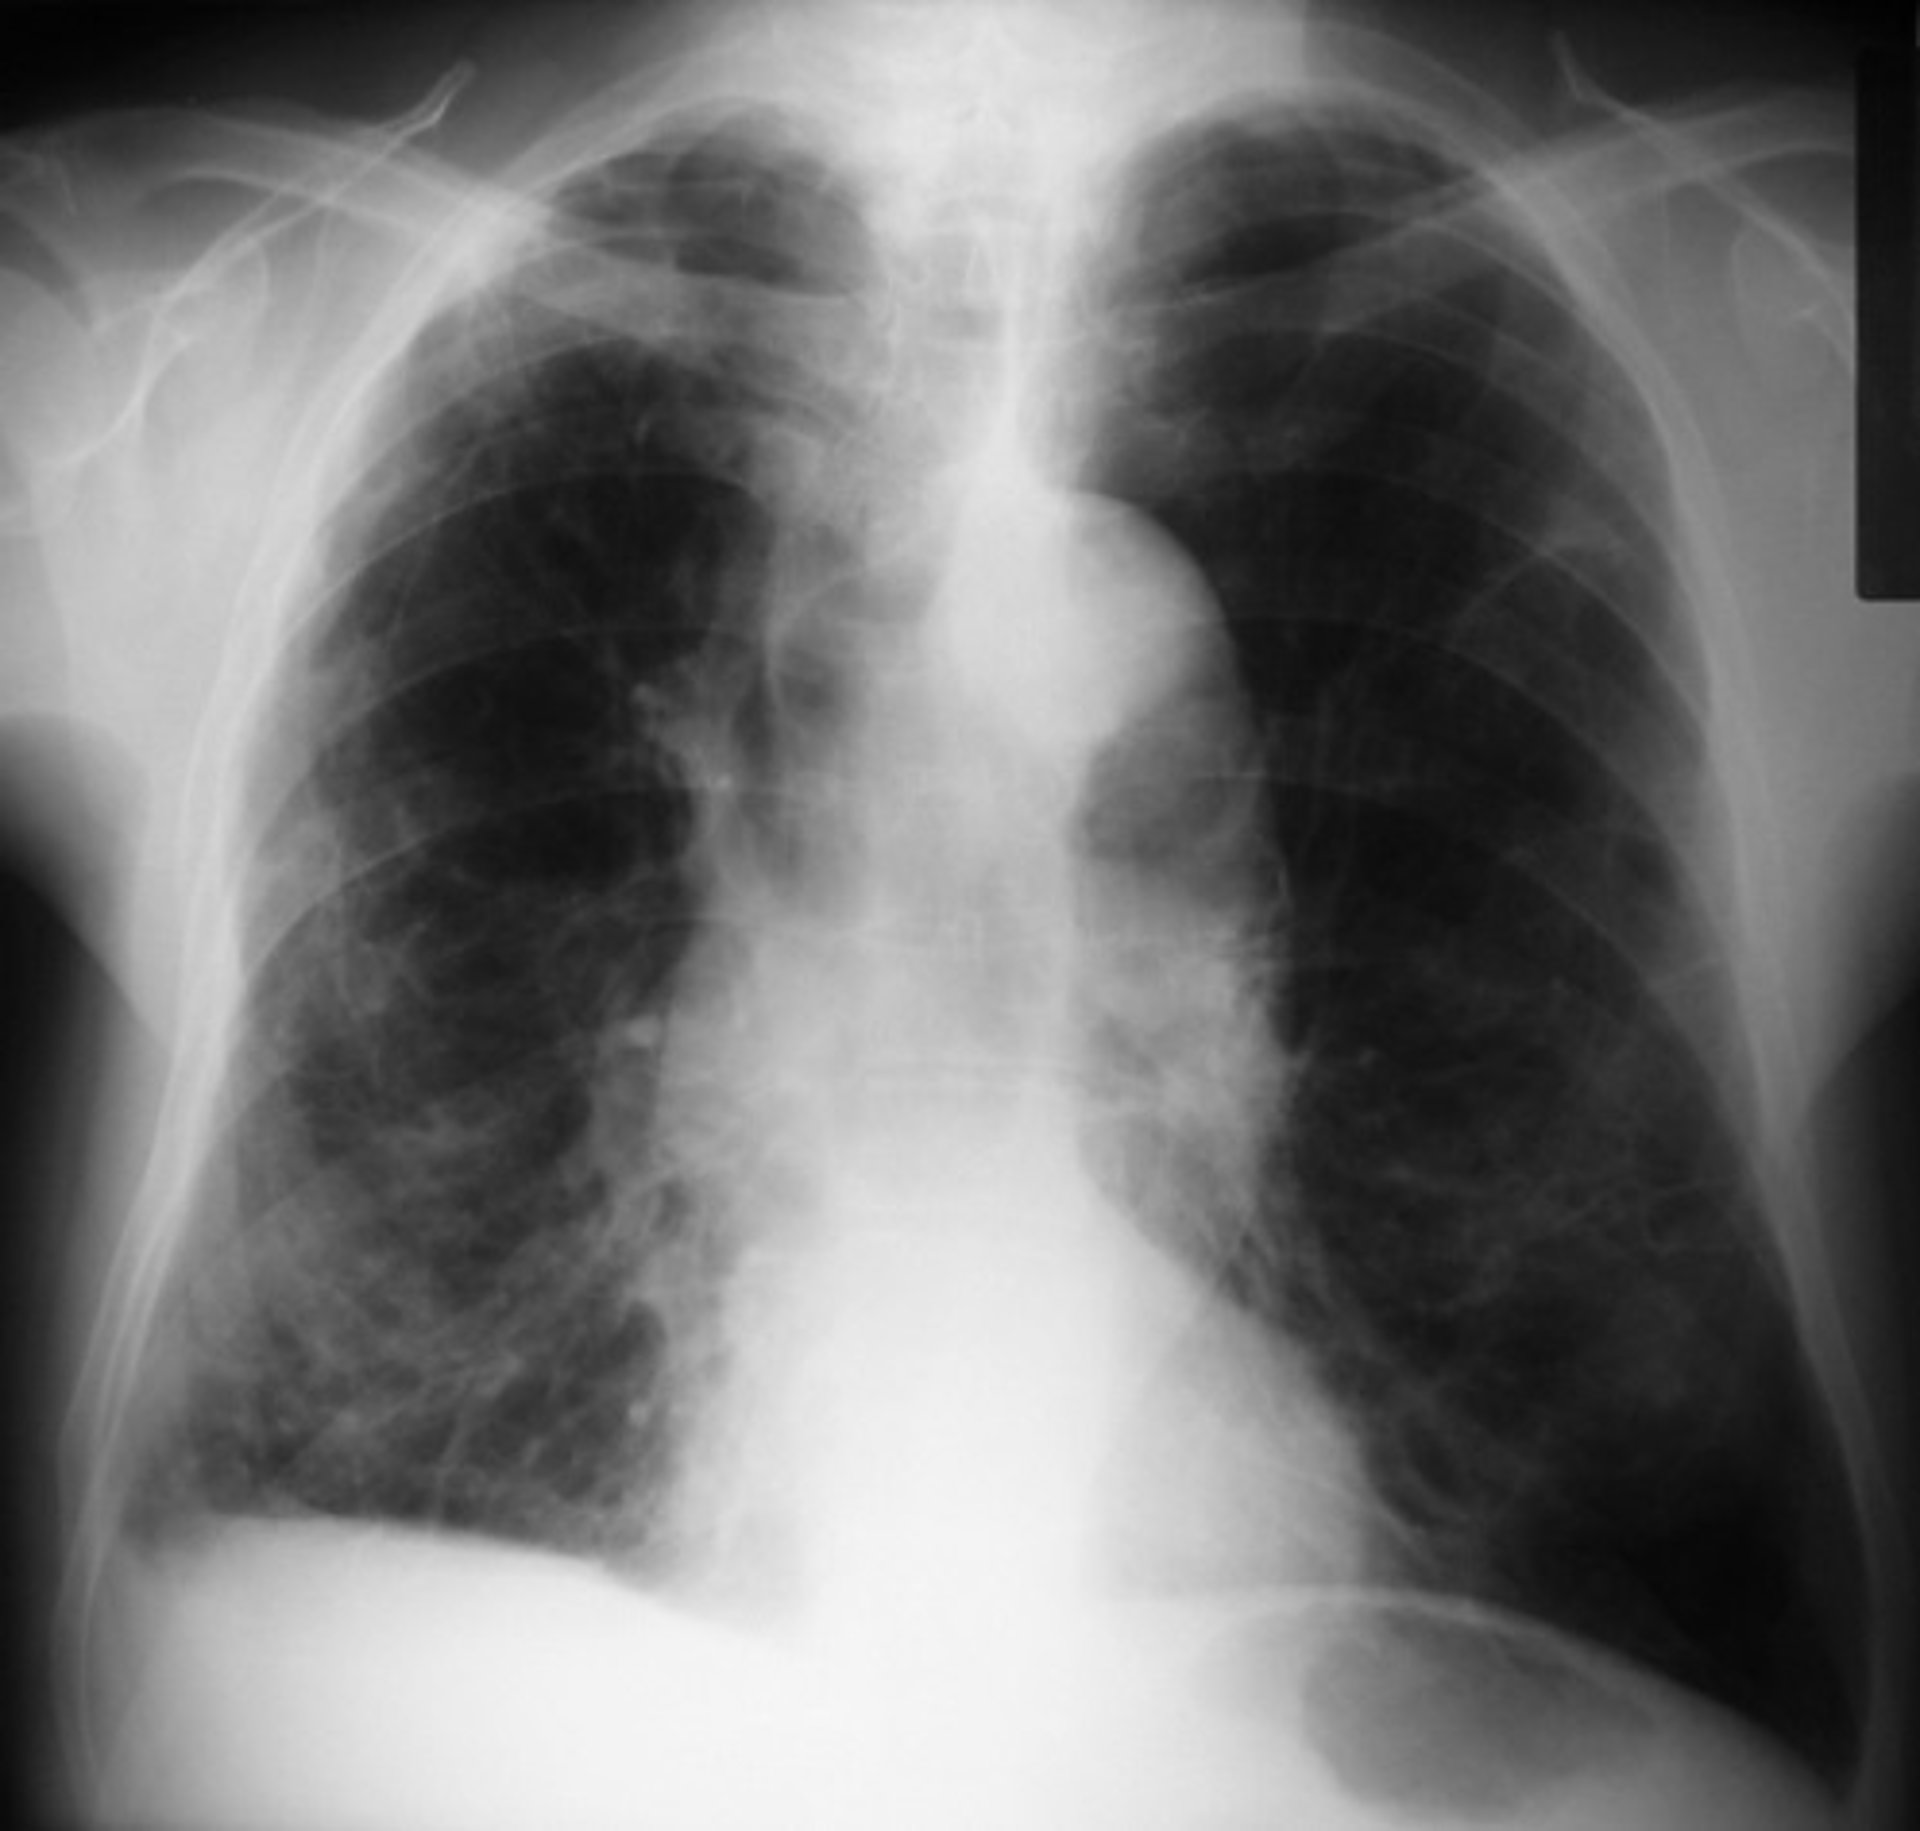

Realizado el 'Retrato Robot' del fumador con EPOC no diagnosticada

EPOC